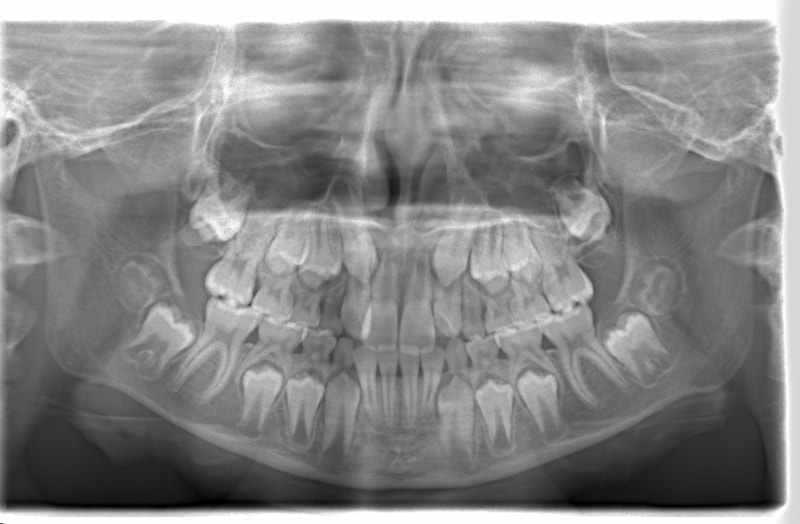

治療開始時

FX(フェイシャルアキシス)は85度なので東洋人の平均値に近く、下顎が前方に過剰成長するリスクは強くはありません。

しかしやはり上顎は劣成長で、下顎が優位な状態ではあります。

上下顎のギャップはありますが、顔面自体の幅径は良好な値を示していますので、スペース不足は拡大することによって解決できポテンシャルはあると考えられます。

左右の非対称もさほど強くありません。

骨年齢は実年齢よりも低めなので、今後下顎の旺盛な成長が見込まれます。

検査時のレントゲン分析では、上下顎の関係は、上顎の劣成長があり下顎前突傾向という値がでておりましたが、前歯ジャンプ後はフェイスマスクの効果もあり、上下顎の関係は正常化しています。

上顎が若干優位になっていますので、今後の下顎の成長のための貯金になっているくらいです。